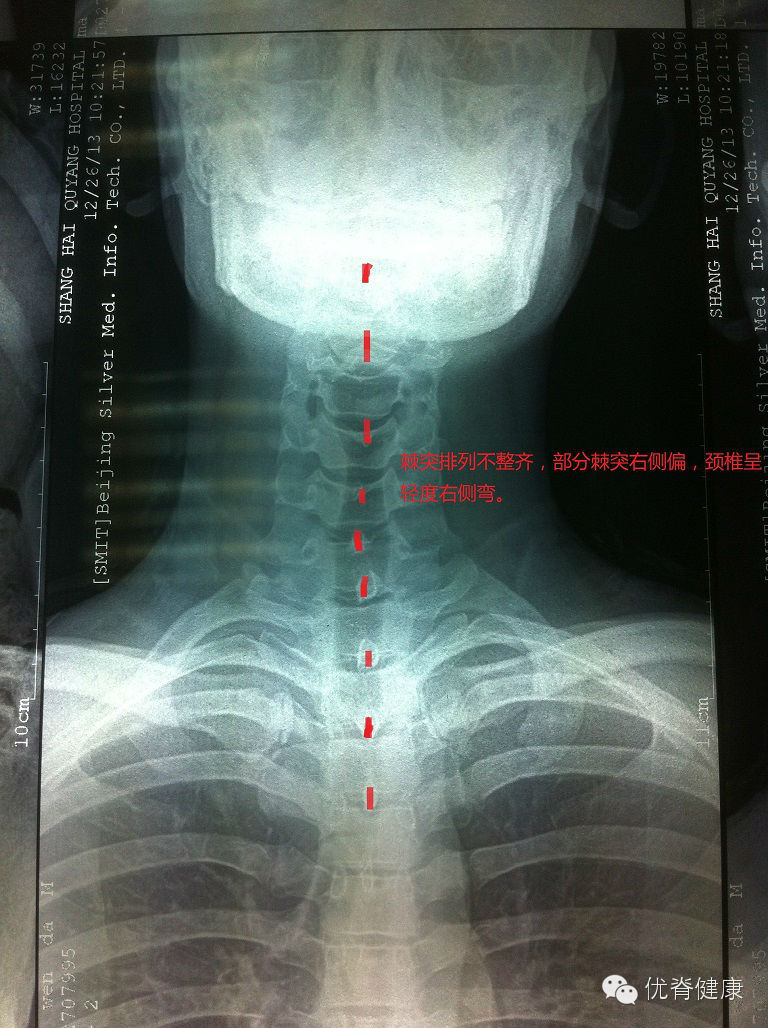

环枢关节错位,颈椎生理曲度反弓,轻度右侧弯,部分骨质增生;腰椎轻度左侧弯,伴骶椎S1隐裂;颈腰部肌群不同程度劳损,以上颈部及下腰部肌群劳损较为明显。

评估分析:颈椎软组织劳损,伴环枢关节错位,颈椎生理曲度反弓,伴轻度右侧弯。腰椎轻度左侧弯,腰肌劳损。